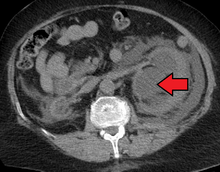

Imaging studies, such as an intravenous urogram (IVU), ultrasound, CT or MRI, are also important investigations in determining the presence and/ or cause of hydronephrosis. Whilst ultrasound allows for visualisation of the ureters and kidneys (and determine the presence of hydronephrosis and / or hydroureter), an IVU is useful for assessing the anatomical location of the obstruction. Antegrade or retrograde pyelography will show similar findings to an IVU but offer a therapeutic option as well. Real-time ultrasounds and color-flow Doppler tests in association with vascular resistance testing helps determine how a given obstruction is effecting urinary functionality in hydronephrotic patients.[12]

The choice of imaging depends on the clinical presentation (history, symptoms and examination findings). In the case of renal colic (one sided loin pain usually accompanied by a trace of blood in the urine) the initial investigation is usually a spiral or helical CT scan. This has the advantage of showing whether there is any obstruction of flow of urine causing hydronephrosis as well as demonstrating the function of the other kidney. Many stones are not visible on plain X-ray or IVU but 99% of stones are visible on CT and therefore CT is becoming a common choice of initial investigation. CT is not used however, when there is a reason to avoid radiation exposure, e.g. in pregnancy.